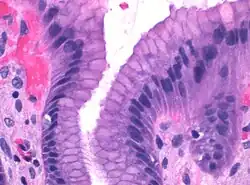

Foveolar cells line the surface of the stomach and the gastric pits. They constitute a simple columnar epithelium, as they form a single layer of cells and are taller than their width. Other mucus-secreting cells are the mucous neck cells in the necks of the gastric glands.[2]: 257

Surface mucous cells have large quantities of mucin granules in their apical (top) surface and project short microvilli into the lumen of the stomach.[2]: 257 Mucins are large glycoproteins that give the mucus its gel-like properties.[3] As mucins are lost during routine histology preparation, they stain pale, but if preserved correctly the cells stain strongly with special techniques like PAS or toluidine blue, the last representing the anionic nature of foveolar cell secretions. Below the mucin granules, surface mucous cells have a Golgi apparatus, the nucleus, and small amounts of rough endoplasmic reticulum.[4]: 577 Mucous neck cells are located within gastric glands. These are shorter than their surface counterpart and contain lesser quantities of mucin granules in their apical surface.[4]: 578